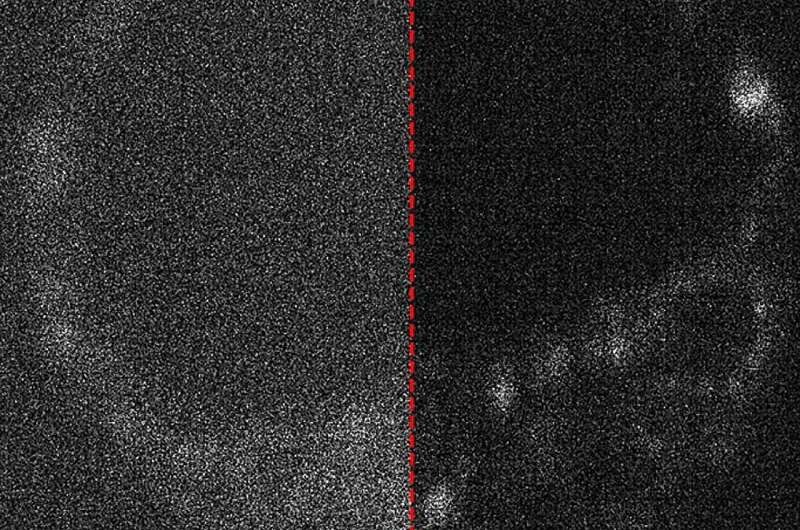

Квантовые камеры впервые использовали для наблюдения за развитием эмбрионов

Исследователи из Университета Аделаиды (Австралия) впервые в мире провели съёмку эмбрионов с использованием камер, разработанных для квантовых измерений. Учёные из «Центра света для жизни» (Center of Light for Life) исследовали возможности применения сверхчувствительных камер нового поколения, способных подсчитывать отдельные фотоны на каждом пикселе, в области биологических наук.

Директор Центра профессор Кишан Дхолакия отметил, что чувствительное детектирование этих фотонов крайне важно для наблюдения за биологическими процессами в их естественном состоянии. Это позволяет исследователям освещать живые клетки очень слабым светом, минимизируя воздействие на них.

Изображение живого эмбриона мыши с оптимизированным захватом и без него. Источник: APL Photonics (2025). DOI: 10.1063/5.0245239 «Повреждение от освещения — реальная проблема, которой часто пренебрегают. Использование минимально возможного уровня освещения вместе с такими сверхчувствительными камерами крайне важно для понимания биологических процессов в живых и развивающихся клетках», — пояснил профессор Дхолакия. Исследовательская группа протестировала технологию для съёмки эмбрионов в рамках доклинических испытаний.

По словам ведущего автора исследования и аспиранта Зейна Петерковича, цифровые камеры достигли такого уровня развития, что фундаментальные физические концепции, включая квантовую механику, становятся важными и актуальными для их работы. «Многие природные соединения в клетках светятся при освещении, и это может многое рассказать об исследуемом объекте, но, к сожалению, сигнал очень слабый», — отметил он.

Анализ изображений стал возможен благодаря сочетанию экспертизы в области оптики, биологии, лазерной физики и микроскопии. Исследователи также изучили возможности использования искусственного интеллекта для удаления шумов с полученных изображений, которые возникают из-за недостаточного количества света при съёмке.

В дальнейшем учёные планируют расширить исследования в область квантовой визуализации, где квантовые состояния света могут быть использованы для получения дополнительной информации об исследуемых образцах. Эта технология открывает новые перспективы для развития методов экстракорпорального оплодотворения и исследования живых клеток.